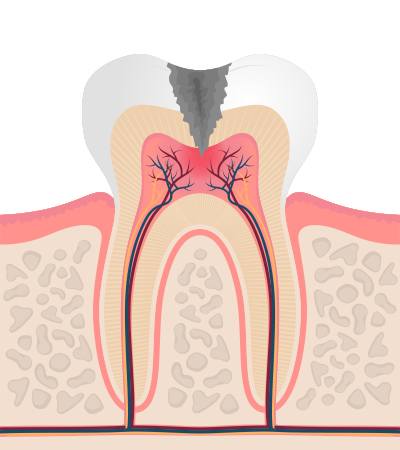

충치의 단계 및 치료법

-

3단계

신경까지 진행 상당한 통증